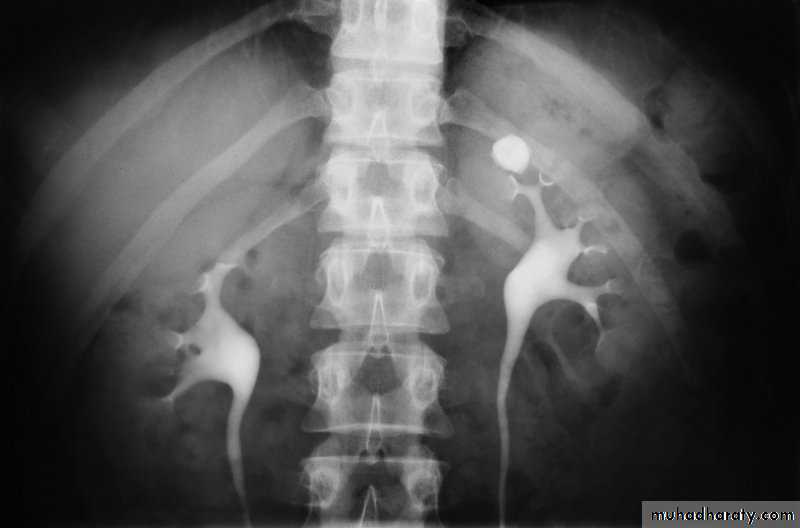

l.V.U. findings:

-Plain film may be useful in demonstrating calculi.-After contrast injection:

Acutely obstructed kidney shows a dense nephrogram (dense opacification of the renal parenchyma).excretion of contrast (opacification of the collecting system which may take many hours), then the level and degree of obstruction can be determined as dilated pelvi-caliceal system and ureter are followed down to the point of obstruction (point of hold up).

Pyeloxinus reflux may result from rupture of a fornix precipitated by contrast-induced diuresis superimposed on the increased hydrostatic pressure of an obstructed pelvicaliceal system. Urine and contrast extravasate into the renal sinus and perirenal space